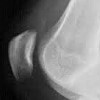

Рентгенография надколенника

Рентген надколенника (коленная чашечка). Метод лучевой диагностики основан на способности рентгеновских лучей проникать в ткани с ослаблением сигнала и последующей фиксацией на черно-белых изображениях. Техника используется для визуализации коленной чашечки, ее внутренней структуры, размера и положения. Он используется для диагностики травматического повреждения коленной чашечки, выявления воспалительных процессов и специфических изменений в коленной чашечке, которые характерны для некоторых нозологий. Любые существующие объемные образования также визуализируются на изображениях, смещение кости и аномалии ее структуры узнаваемы. Рентгенограмма коленной чашечки сделана изначально без какой-либо предварительной подготовки. Требуется особая укладка пациента. Обследование часто бывает двусторонним и может сочетаться с рентгенологическим исследованием коленного сустава.